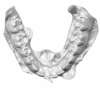

Décalage maxillo mandibulaire traité par gouttières

B-Début 2